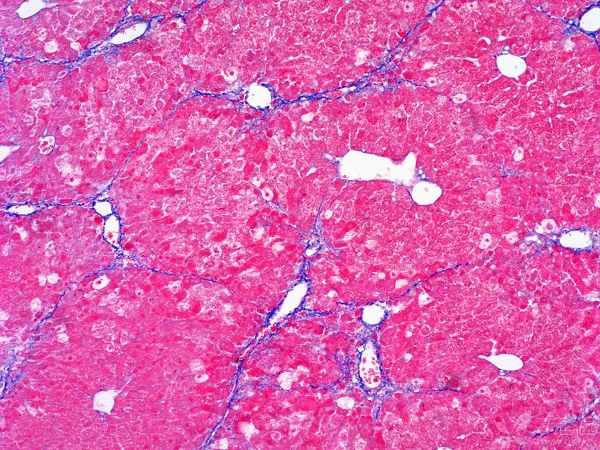

- Masson三色染色:量化胶原沉积(蓝色区域)。

纤维化组织MASSON染色结果

纤维化组织中,MASSON染色会呈现出明显的红色或紫色区域。这些区域代表了胶原纤维的增生和沉积,是纤维化病变的典型表现。通过观察这些区域的分布和范围,可以初步判断纤维化的程度和范围。